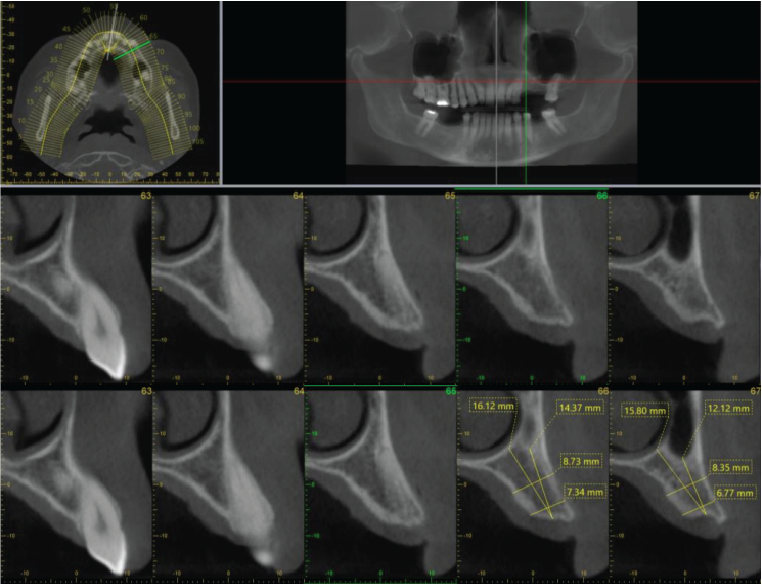

Periodontal bone levels are mainly normal or show mild bone loss, but there is greater bone loss associated with UR8 and UR7 and incidental finding of caries. UL4, UL5, UL6 sites have a mature alveolar ridge. No retained roots or bony pathosis. Selected images 3 are bucco-palatal cross-sections across the site. Bone height to the antral floor steadily falls moving distally across the site. There is a short transverse septum at the maxillary antral floor above the palatal side of UL5 site, which should not be relevant to any sinus lift procedure being planned. The alveolar bone quality appears satisfactory, with fairly dense trabeculation and well-defined cortices. The LL6 site has a mature alveolar ridge with no retained roots or bony pathothis. LL7 is mesially inclined, so that its crown overhangs the site. Selected images 4 are bucco-lingual cross-sections across the site. The alveolar ridge has a broad crest. There is a mild lingual undercut, with a lingual concavity present mesially in the site and in the premolar region. The lingual concavity of the submandibular fossa appears towards the distal end of the site. The ID canal is easily identified, lying quite low in the bone. The mental canal is in the plane of LL5. Bone quality is satisfactory, with well-defined thick cortices and fairly evenly trabeculated medullary bone.

Image 3

Image 4